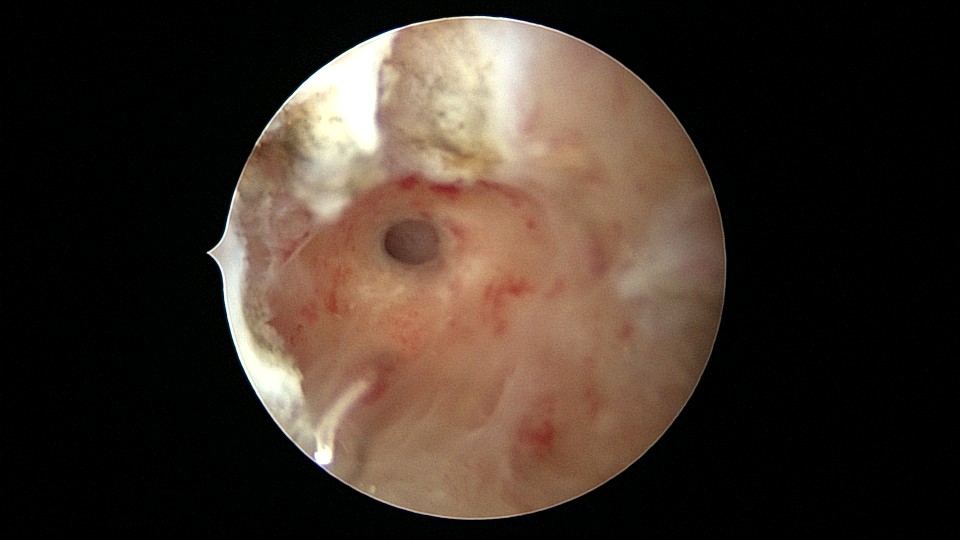

患者33岁,G5P2,顺产2次,胎停清宫后月经量减少,外院B超提示宫腔粘连。2021年5月宫腔镜探查,宫腔重度粘连,宫腔狭小,右侧输卵管开口可见,左侧输卵管开口未见,单极电针分粘,恢复宫腔形态,显露左侧输卵管开口(僵硬)。2021年6月宫腔镜二探取球囊,宫腔形态正常,双侧输卵管开口可见,宫内膜薄。2022年7月自然妊娠,2023年3月孕39+周顺产分娩。现38岁,G6P3,顺产3次。